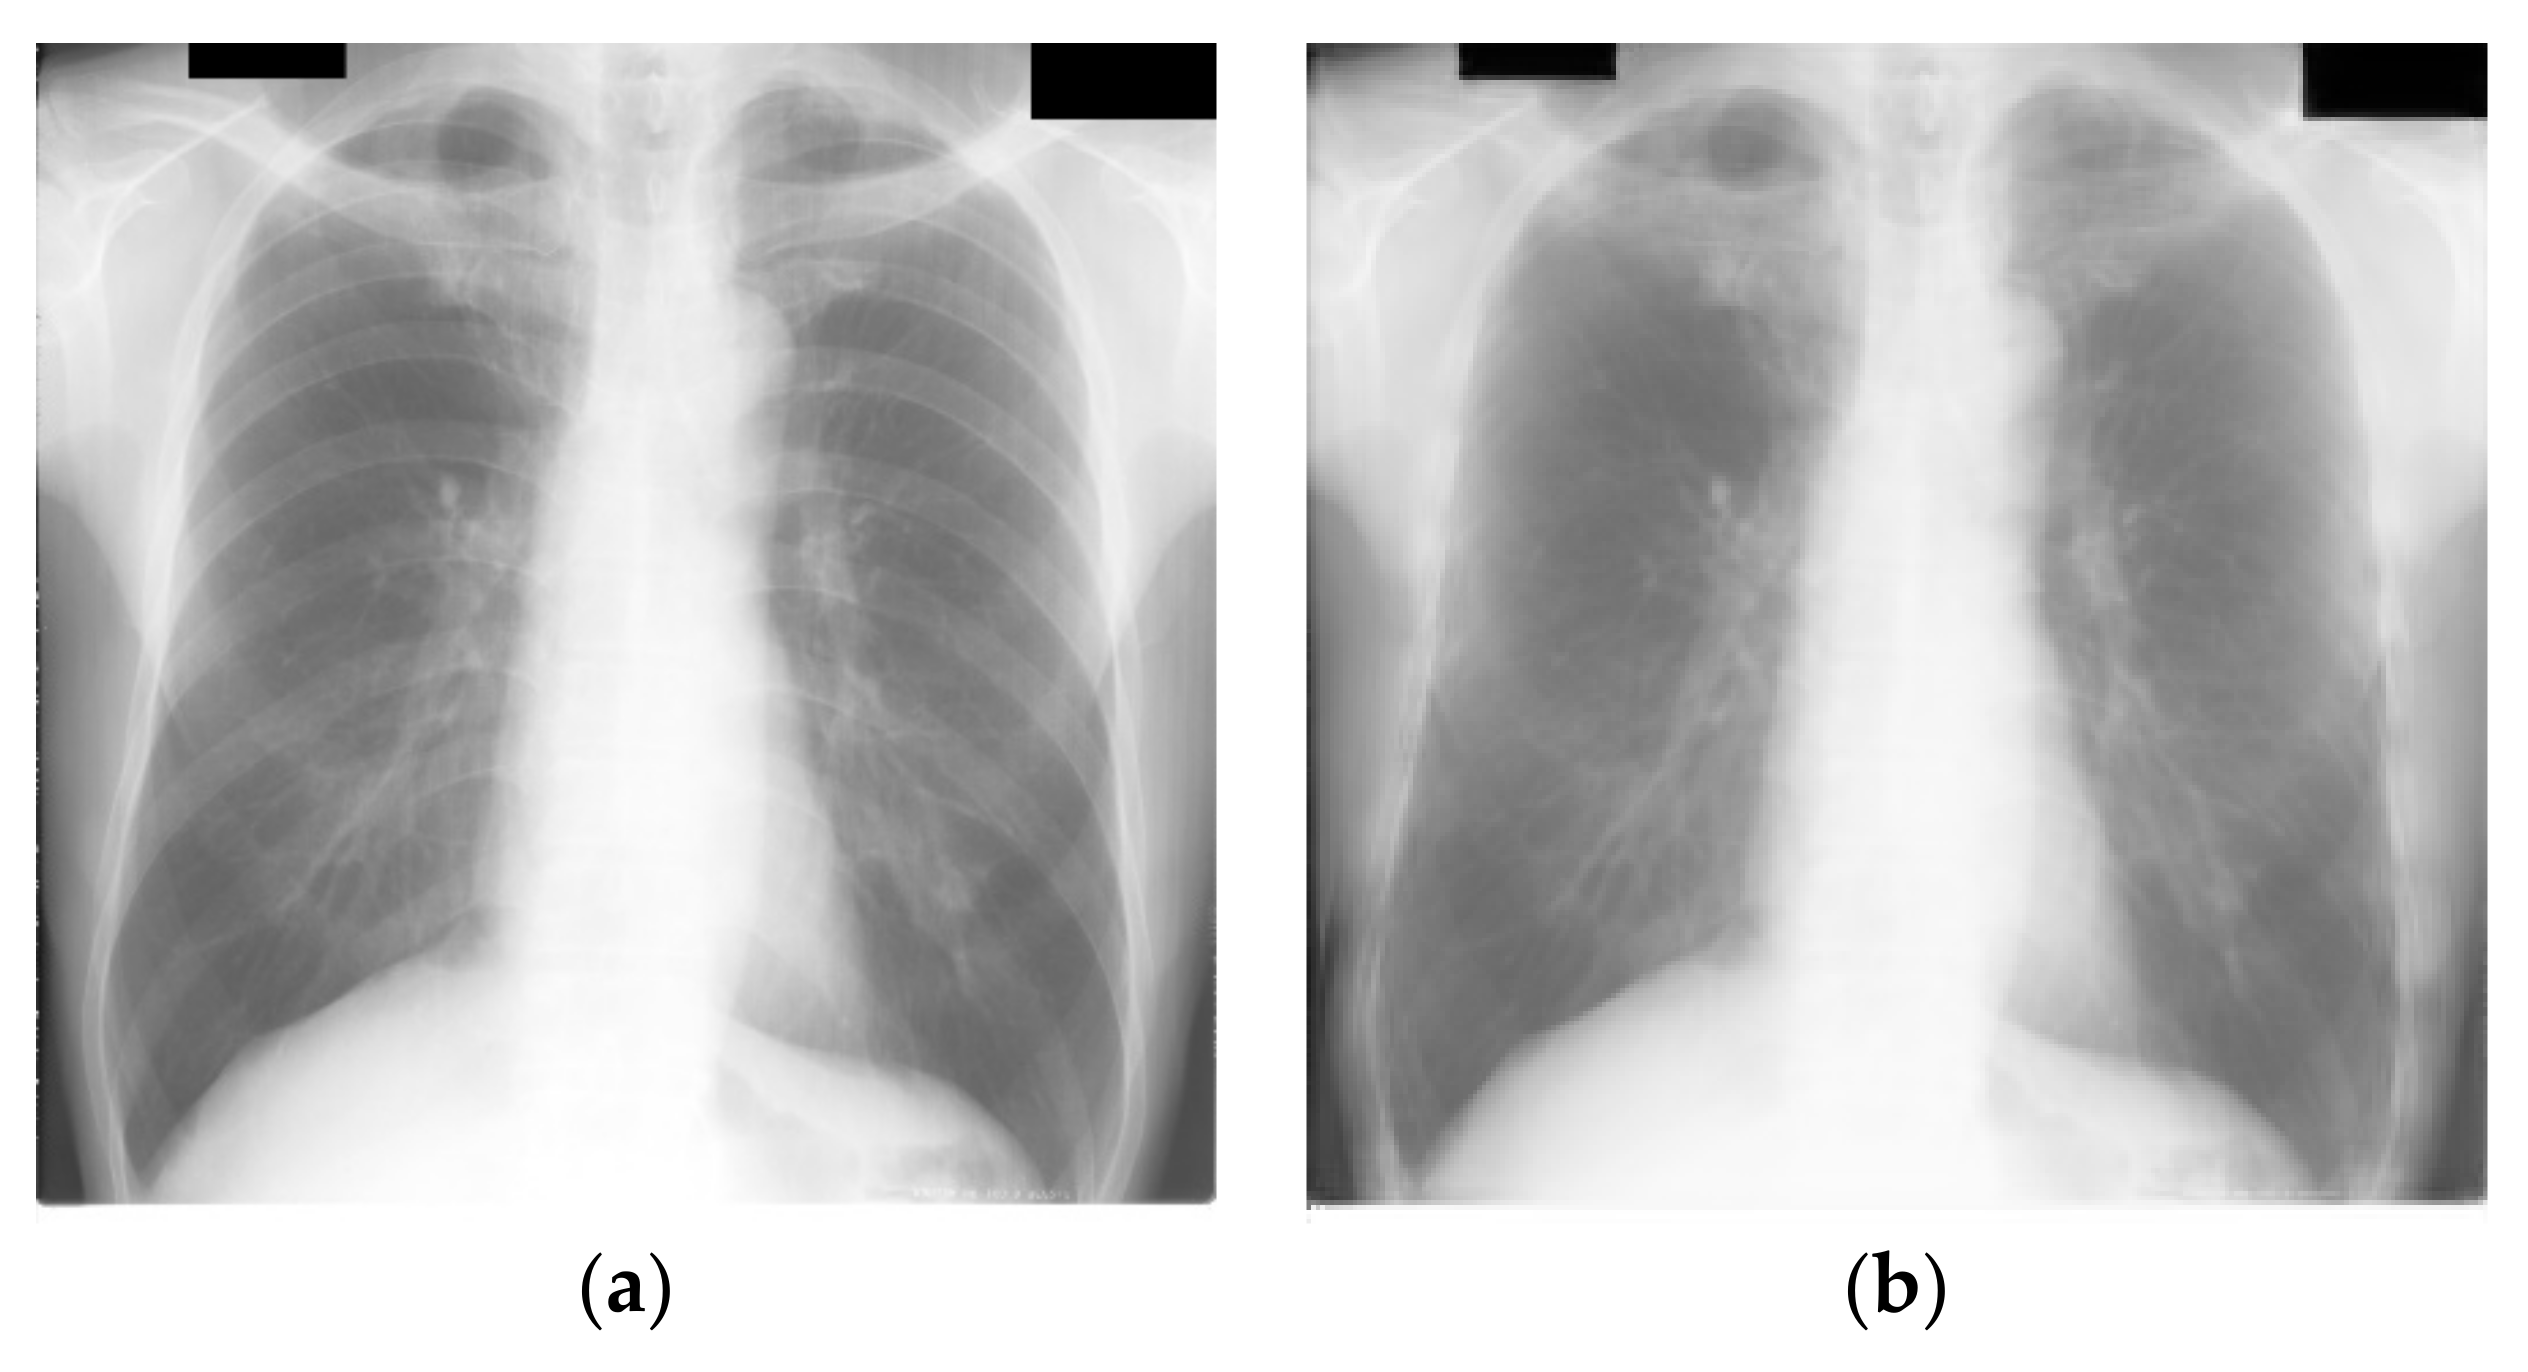

| Dataset | Nodule Image Count | Non-Nodule Image Count | Image Size/Format | Label Accuracy AUC-ROC |

|---|---|---|---|---|

| JSRT | 154 images from 154 patients | 93 images from 93 patients | Universal Image Format 2048 × 2048 12-bit grayscale | 20 radiologists from 4 institutions. 0.833 ± 0.045 |

| LIDC | 280 images from 157 patients | 0 | DICOM Extracted and compressed to 512 × 512 PNG using Pydicom [53] | Not provided |

| Experiment | Segmentation | Cropping | Rib Suppression | Sample Image |

| A | False | False | False | ![]() |

| B | False | False | True | ![]() |

| C | True | False | False | ![]() |

| D | True | False | True | ![]() |

| E | True | True | False | ![]() |

| F | True | True | True | ![]() |